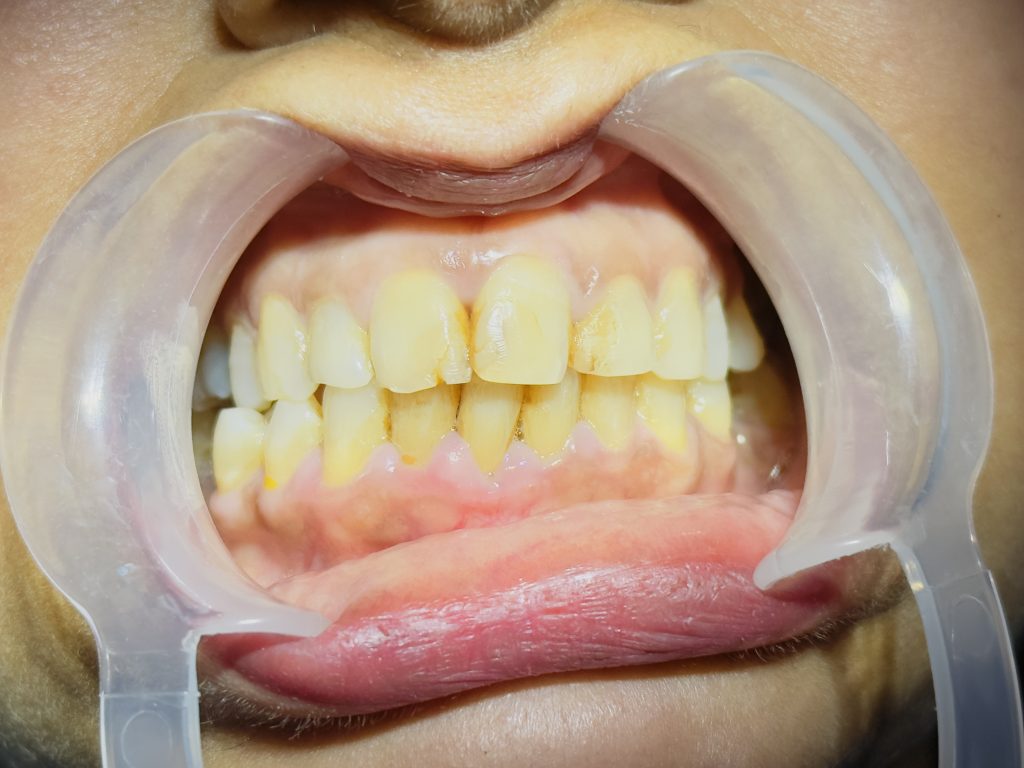

This case presents a full smile rehabilitation using lithium disilicate (E.max) crowns in a patient with a history of dental trauma and severely discolored anterior teeth. The patient had previously undergone MTA apexification to manage an open apex. Due to time constraints and the patient’s refusal of orthodontic treatment, an interdisciplinary digital restorative approach was undertaken. The treatment included non-vital internal bleaching, digital smile design (DSD) using Exocad, and minimal preparation E.max crowns to restore function, symmetry, and esthetics.

- Moderate discoloration of tooth #11 and #21.

- Slight midline discrepancy; patient declined orthodontic correction.

- Post-traumatic discoloration due to pulpal necrosis.

- Residual esthetic defect after apexification.

- Asymmetrical incisal edges, smile cant, and uneven gingival margins.